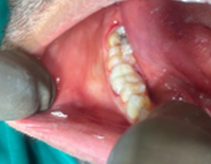

Figure 2a: Before treatment clinical photograph #36

- #26, #36 – Root piece (Figure 2a and 2b)